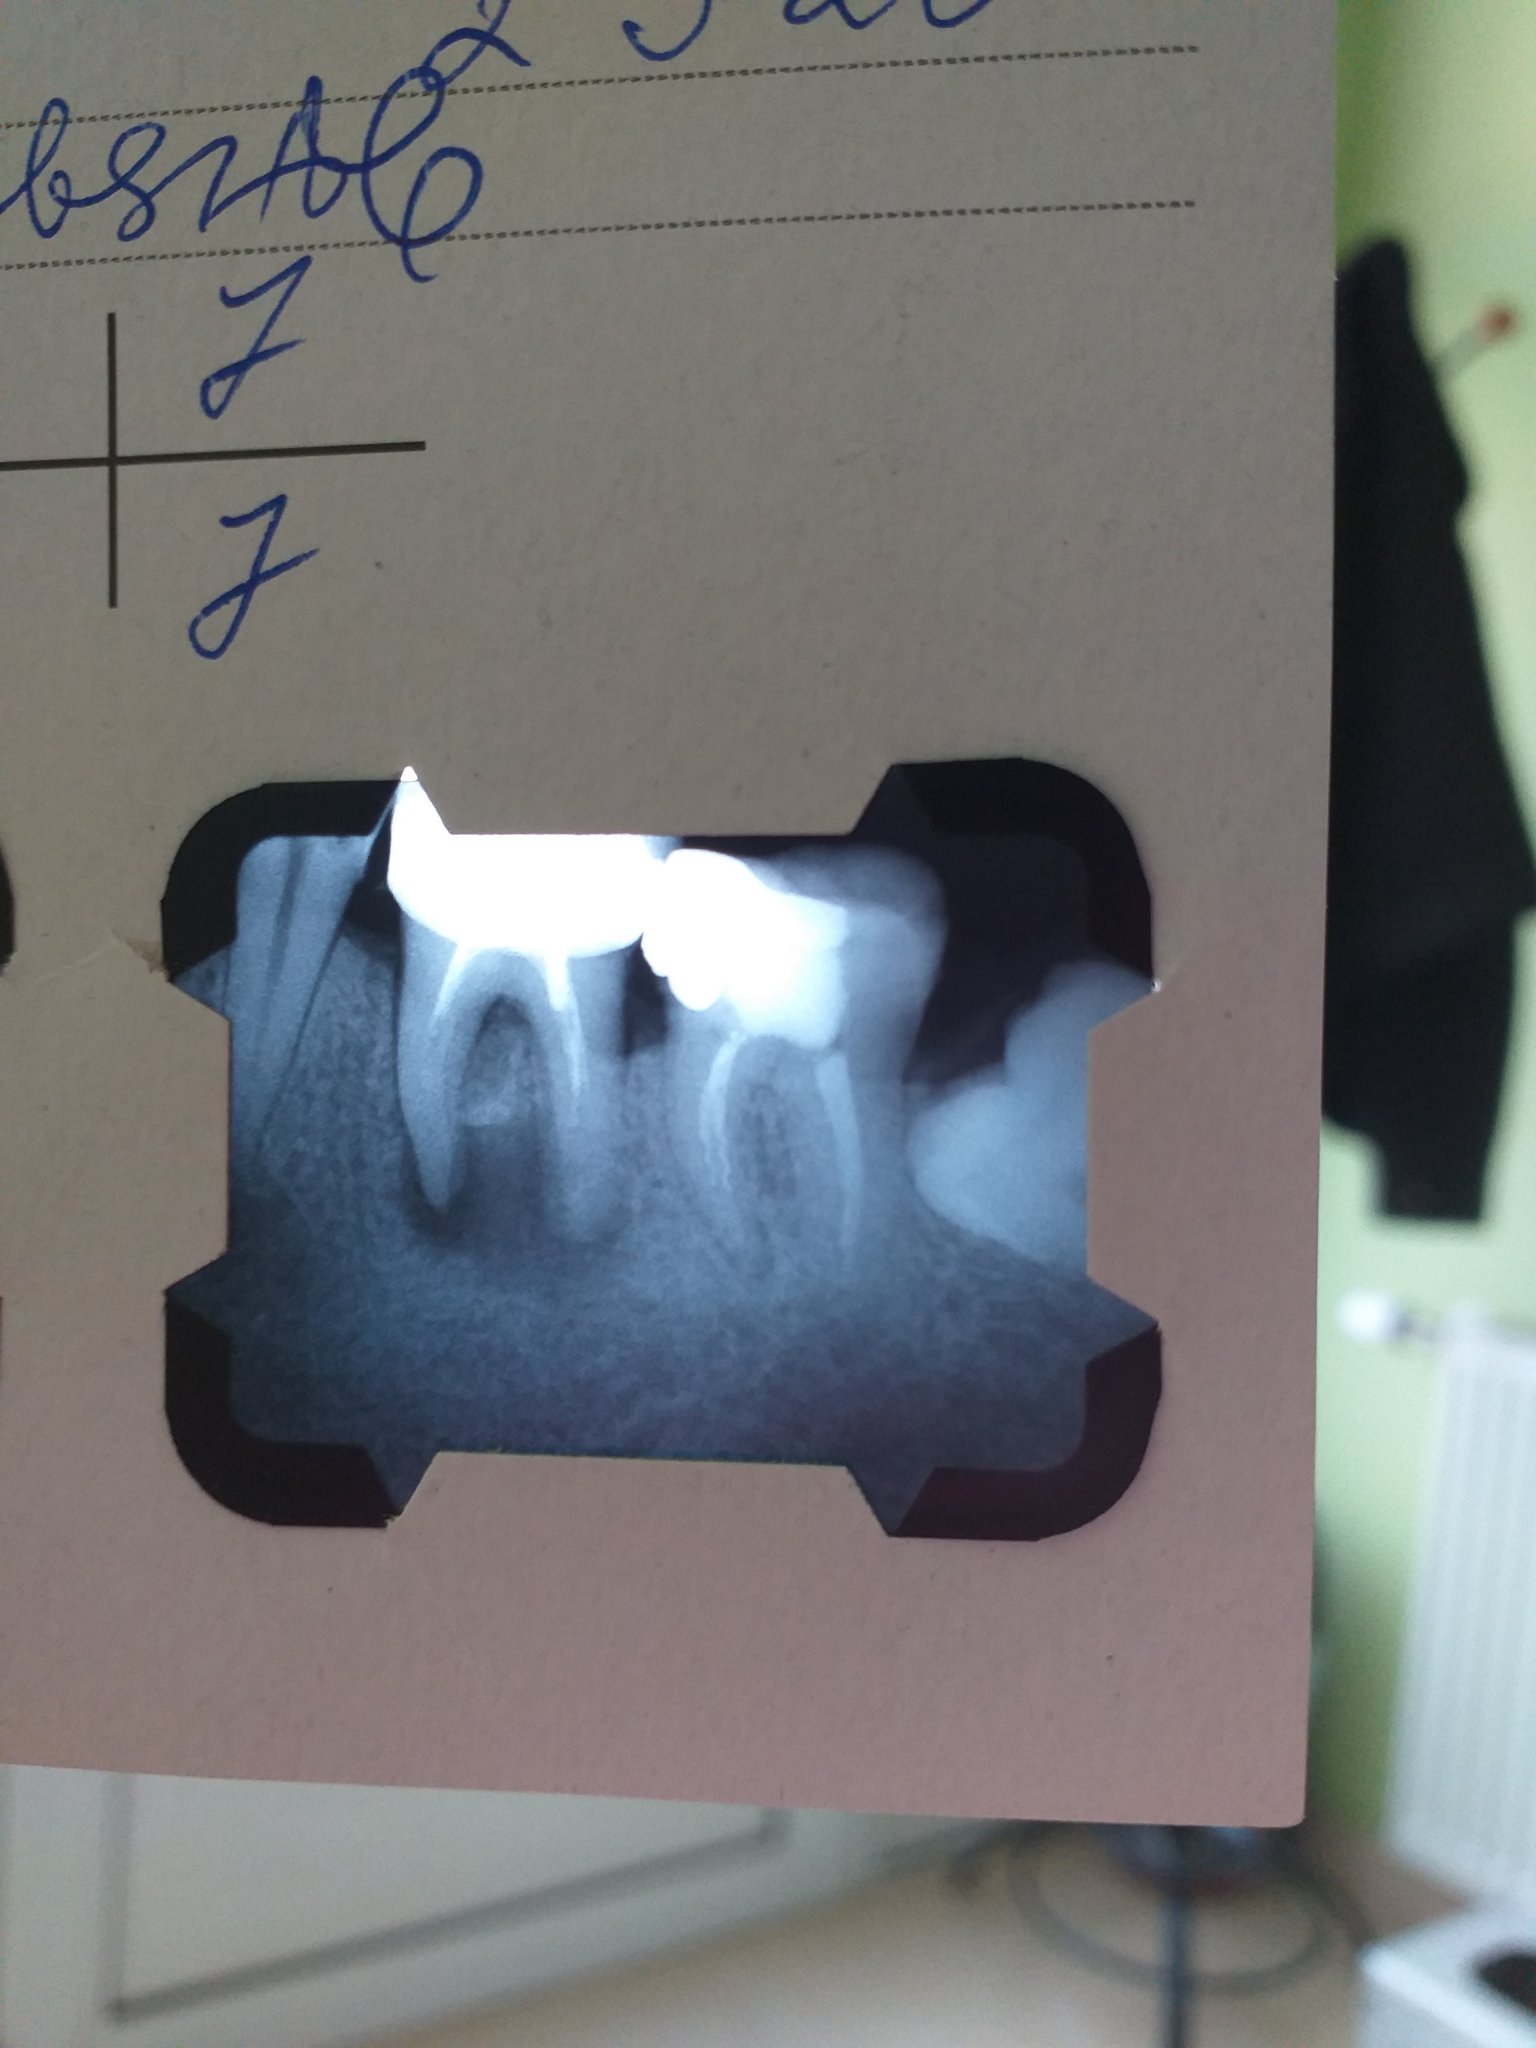

Здравейте, днес си правих снимка да видя дали ми е запълнен 7 зъб и се оказа че имам гранулом на 6. Зъбът и правен преди 15 г с металокерамика и тогава съм правила снимка но нищо не са ми казвали ( за проблем)....гледах че не е запълнен докрай ! Има ли зъболекари които влизат във форума и могат да ме посъветват какво   да направя. Доста съм отчаяна ,дали ще се излекува , а и от финансова гледна точка дали ще излезе много скъпо?

Първо искам да кажа, че всичко е лечимо и няма нужда да се вадят зъби!

В момента наистина има голям гранулом на 6-ти зъб и не е запълнен до края на каналите. Вероятно това е една от причините за появата му. Зъбът според мен изглежда напълно лечим. Трябва да се проведе кореново релечение, да се изгради зъба и след това да се смени короната. Няма да е много евтино, защото изглежда сравнително тежко положението и ще изисква адекватно лечение.

За съжаление задният ви зъб също не е запълнен добре. Освен това в предния му (ляво на снимката) корен има счупени два инструмента в каналите (пълнители). Те трябва да се извадят и да се направи релечение и на него.